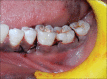

Periodontal regeneration is defined as the reproduction or reconstitution of a lost or injured part to restore the architecture and function of the periodontium. The ultimate goal of periodontal therapy is to regenerate the lost periodontal tissues caused by periodontitis. The most positive outcome of periodontal regenerative procedures in intra bony defect has been achieved with bone grafts. For complete regeneration, delivery of growth factors in a local environment holds a great deal in adjunct to bone grafts. Platelet rich fibrin (PRF) is considered as second generation platelet concentrate, consisting of viable platelets, releasing various growth factors. Hence, this case report aims to investigate the clinical and radiological (bone fill) effectiveness of autologous PRF along with the use of alloplastic bone mineral in the treatment of intra bony defects.